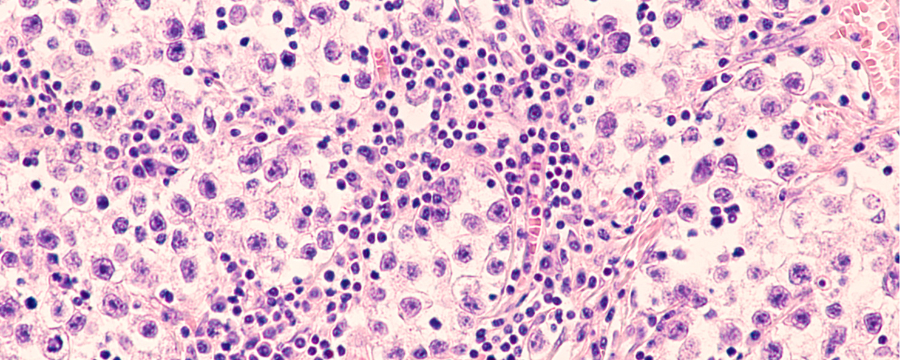

Seminoma

¿Qué es Seminoma?

El seminoma es un tipo de cáncer que tiene su origen en los testículos y cuyas causas no están del todo claras en la actualidad. Los pacientes afectados suelen ser diagnosticados en torno a los 40 - 50 años y conviene detectarlo a tiempo para poder iniciar un tratamiento que mejore el pronóstico. Este suele ser muy positivo.